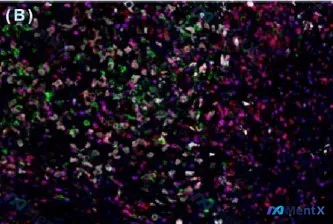

最近看到一份脾脏滤泡树突状细胞肉瘤(FDCS)的多重免疫荧光(MIF)资料,觉得挺有启发性,整理一下思路和大家分享。 --- 先看影像基础信息 这张是 五重免疫荧光染色: - CD3(品红)、CD4(红)、CD20(绿)、CD56(青)、FoxP3(黄) - 没有用传统的 H&E,而是直接看蛋白标记...